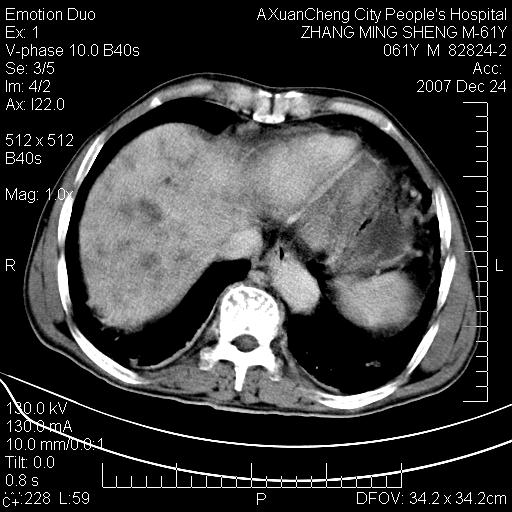

标题: CT11031:M61Y,胰腺占位 [打印本页]

标题: CT11031:M61Y,胰腺占位

大家侃侃门静脉和胆管系统怎么回事,肝内转移?

1,肝硬化,脾大.

2,肝内多发结节状低密度占位,伴门脉及肠系膜上v栓子形成.考虑a;门脉及肠系膜上v血栓后肝改变.b;弥漫型肝癌伴门脉及肠系膜癌栓.

肝硬化,门脉高压,脾肿大;弥漫性肝癌,肝内、门脉、腹膜后淋巴结转移,肝内外胆管扩张,胰头区占位,建议mr检查

胰腺癌伴肝内转移;门脉、肠系膜上v癌栓形成。

考虑为:胰腺癌伴肝脏转移、腹膜后淋巴结转移,门静脉及肠系膜上静脉瘤栓形成。

胰体尾癌伴肝内转移,门静脉及肠系膜上静脉瘤栓形成.